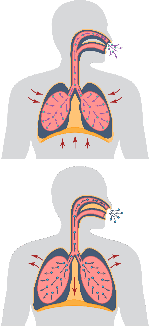

MECHANISM OF ACTIONS (MOA)

EA 575® is also unique to help improve respiratory function in patients with bronchitis.

- The EA 575® is an active ingredient from natural ivy leaf which liquefies the sticky mucus trapped in the air passages of the lungs.

- It then acts as an expectorant, allowing the mucus to be coughed up more easily.

- As the air passages relax and widen, you are able to breathe better and more comfortably.